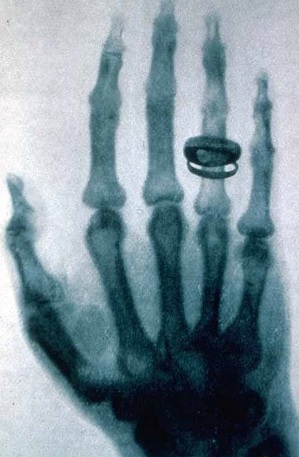

Vieną katodinį vamzdelį Rentgenas apsuko juodu popieriumi. Patalpoje buvo visiškai tamsu. Staiga mokslininkas pastebėjo žalsvą švytėjimą, sklindantį nuo fluorescencinių kristalų. Švietė ir ekranas, padengtas bario junginiu. Tomis priemonėmis buvo tiriami katodiniai spinduliai – jų veikiamos fluorescencinės medžiagos imdavo švytėti. Tačiau dabar katodiniai spinduliai negalėjo prasiskverbti pro stiklą ir popierių, be to, juos sugerdavo netgi nedidelis oro tarpas. Ar iš vamzdelio iš tikro sklido kažkokie spinduliai? Rentgenas kyštelėjo ranką tarp vamzdelio ir ekrano – ekrane išryškėjo rankos siluetas. Susijaudinęs mokslininkas išjungė elektros srovę, einančią per vamzdelį, ir kristalai iškart nustojo švytėti. Rentgenas vėl įjungė srovę – kristalai vėl sušvito. Jis suprato, kad iš vamzdelio iš tikro sklinda kažkokie nežinomi spinduliai, - ir kad jis atrado naują reiškinį. Roentgen X-ray picture of the hand of his wife, taken 23 January 1896

Po 50 d. įtempto darbo Rentgenas pagaliau atskleidė savo paslaptį žmonai Bertai: paprašė ją palaikyti rankos plaštaką ant fotografinės plokštelės. Kai ją išryškino, nustebusi Berta joje išvydo kaulų atvaizdą su vestuviniu žiedu. Netrukus Rentgenas šią nuotrauką pademonstravo Viurcburgo1) fizikų ir medikų draugijos nariams. Jis parengė pranešimą apie naujos rūšies spindulius. Atradimas buvo iškart pripažintas, pranešimas iškart išleistas atskira brošiūra. Tas pranešimas yra pavyzdys, kaip labai svarbų dalyką galima pasakyti labai glaustai – 17-a trumpų tezių, išdėstytų tik keliuose puslapiuose. Netrukus brošiūra buvo išversta į anglų, rusų, prancūzų, italų kalbas.

Visuotinė sensacija kilo, kai Bertos plaštakos nuotrauką pirmame puslapyje išspausdino Vienos laikraštis. Prasidėjo vieši bandymai su spinduliais, vadintais Rentgeno vardu. Gyvo žmogaus kaulų nuotraukos keldavo sąmyšį: vieni gėrėjosi atradimu, kiti jį smerkė, žmogaus tyrimą rentgeno spinduliais laikė nepadoriu dalyku, netgi siūlė atradėją nubausti mirtimi. Kažkokia anglų firma ėmė reklamuoti baltinius, apsaugančius nuo šių spindulių. Pasirodė pranešimų apie dar keistesnių spindulių atradimus.